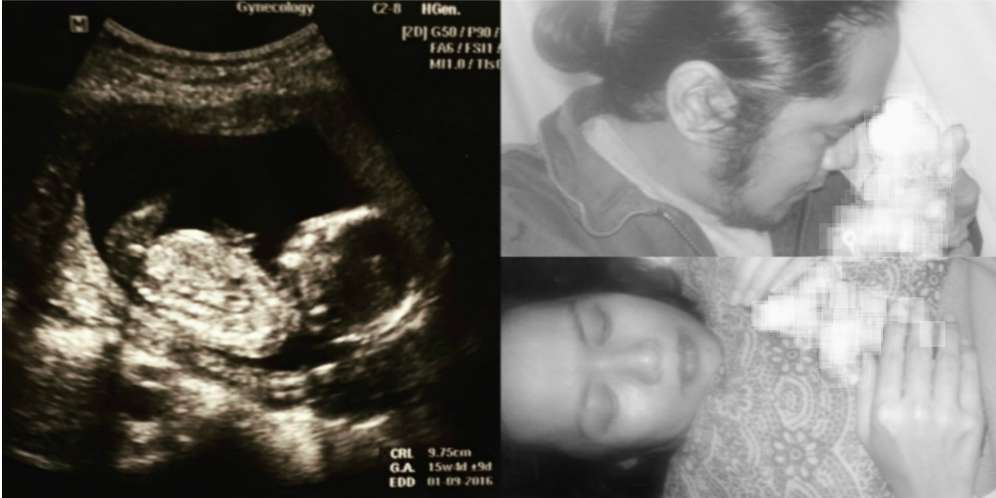

Dream - Duka mendalam dirasakan keluarga penyanyi Dea Mirella, mantan personil grup 'Warna' ini kehilangan sang buah hati yang baru saja lahir. Kabar ini datang dari suami Dea, Roy Hasby, momen bersama bayi yang lahir prematur itu diunggahnya di akun instagram miliknya.

Terlihat dalam foto Dea dan Roy sedang memeluk bayi mungil yang diketahui berjenis kelamin lakii-laki. Menurut Roy bayi yang diberi nama Radja Amundra Hasby itu tidak bisa bertahan akibat sesak setelah dilahirkan.

Dream - Awan hitam menyelimuti hati Penyanyi Dea Mirella dan suami, Roy Habsy. Lantaran anak keduanya meninggal dunia beberapa jam setelah dilahirkan. Menurut manager Dea, Iko Hafid anak kedua Dea yang masih merah berjenis laki-laki itu lahir prematur.

" Iya meninggal pagi. Bayinya lahir prematur," ujar Iko kepada wartwan, Sabtu 23 April 2016.

Menurut Iko Dea dilarikan ke rumah sakit kawasan Bekasi karena pecah ketuban. " Ketubannya pecah, di bawa ke rumah sakit. Itu dua hari sebelum meninggal," ujar Iko.

Menurut Roy bayi yang diberi nama Radja Amundra Hasby itu tidak bisa bertahan akibat sesak setelah dilahirkan. " RIP my beloved Son Radja Amundra Hasby - 21 April 2016 (08.23 wib)," tulis Roy.

Dea mengandung mendiang Radja di usianya yang menginjak 41 tahun. Menurut suami Dea, bayinya tidak sanggup bertahan akibat sesak. " Cuma beberapa jam saja kamu ada melawan sesakmu, dan cuma beberapa menit saja dedek genggam telunjuk ayah. Dedek Radja Amundra Hasby sudah tenang di surga. Ayah dan mama serta kakamu melody rindu kamu dek. RIP my beloved Son Radja Amundra Hasby - 21 April 2016 (08.23 wib)," tutur Roy di akun instagramnya.